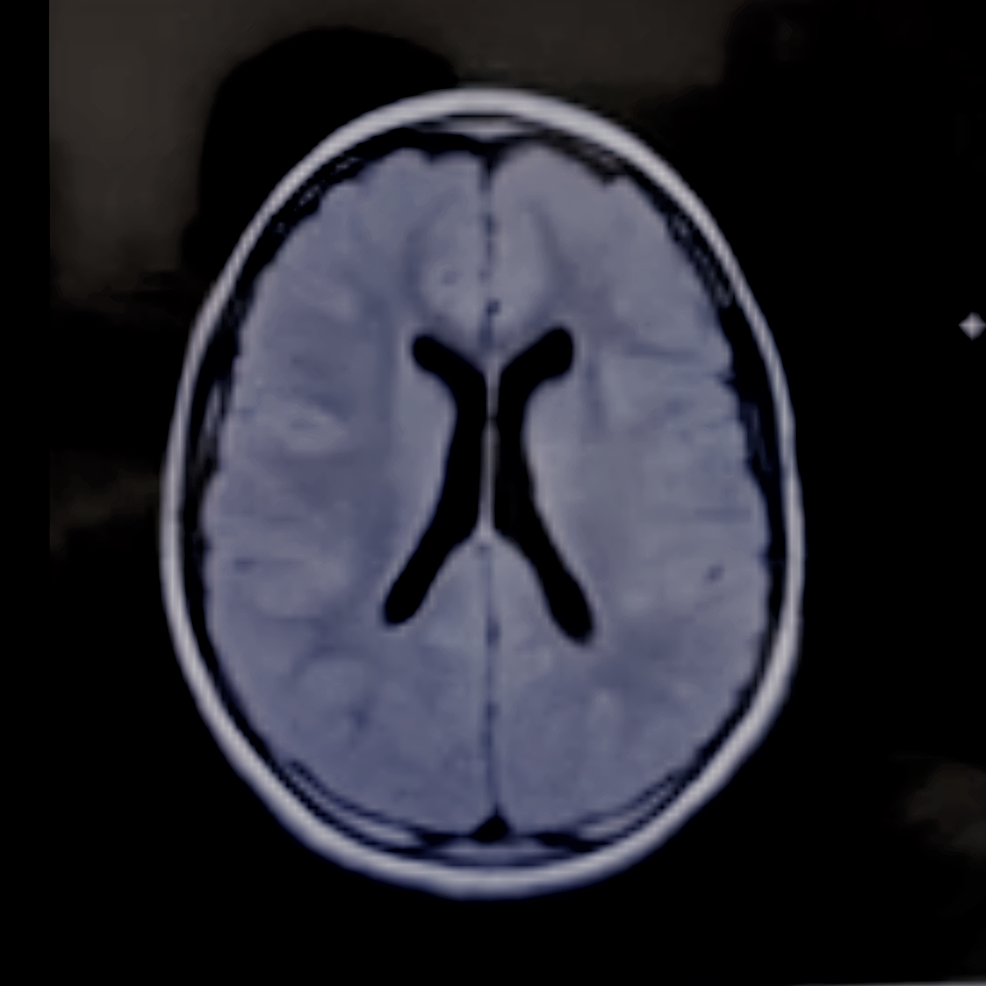

- A key test for identifying multiple sclerosis during diagnosis, or to confirm a relapse, is magnetic resonance imaging MRI.